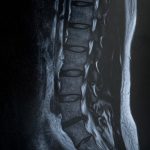

手術後のヘルニアの状態。症状について。 2012年8月12日(日) 椎間板ヘルニアMED(内視鏡下椎間板摘出術)法による手術のあと丸二日...

椎間板ヘルニア入院体験記:終わりに 人生初の入院が椎間板ヘルニアの検査入院、恐れていたミエログラフィーという検査をし、1ヶ月後に再度入...